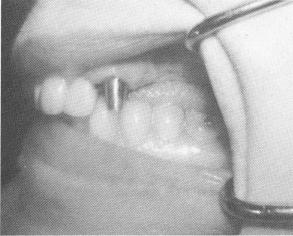

Fig. 13-50. A left cuspid with a completely horizontal fracture of its root midway between its apex and cementoenamel junction was fitted for a gold post prior to further supporting it with an endodontic root stabilizer.

whose root was completely fractured horizontally half-way down its length. The cuspid was first prepared (Fig. 13-50) and then a vent-plant was placed behind it (Fig. 13-51) . After impressions were made, the apical half of the cuspid root was removed through the buccal plate of bone and the endodontic pin implantation performed (Fig. 13-52). A gold post was cemented over the cuspid root and a veneer casting placed over it. Then a gold coping was placed over the vent-plant post. An alginate impression of the opposing jaw, a wax interocclusal record of centric relation, and a plaster index picking up the cuspid casting and implant coping were made for completing the bridge. The bridge was tried and cemented (Fig. 13-53) and a triplant added posteriorly for additional support (Fig. 13-54) . The superstructure was then cemented (Fig. 13-55) .